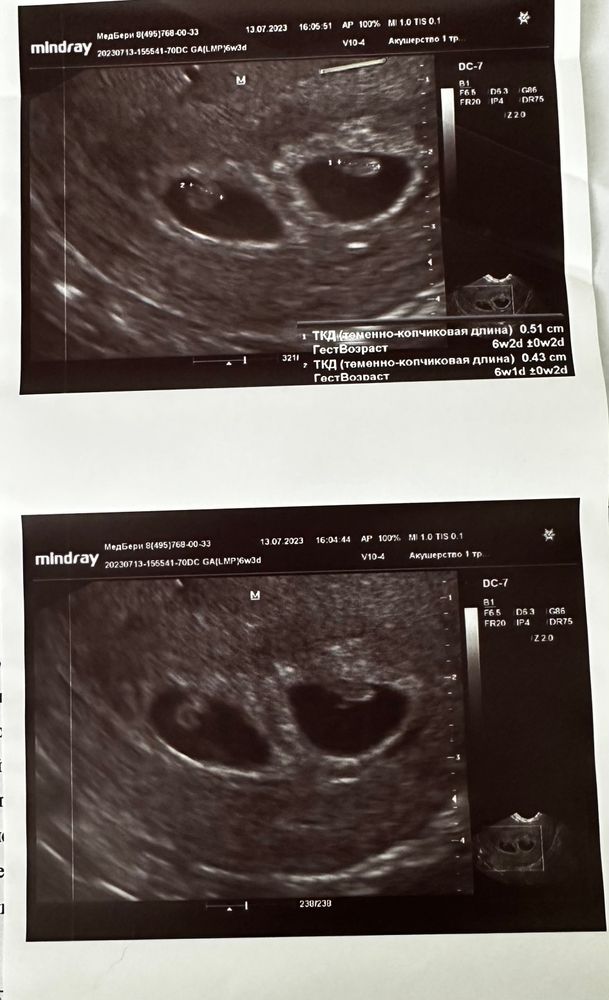

Ре назначила УЗИ на 21 дпп. Мое было удивление когда прижились оба. Сказала, что в 1 ПЯ что то виднеется, а второе плохо видно. Смотрела она через живот. Потом сказала прийти на 26 дпп, там уже опытный врач посмотрит. Счастью не было предела) Тогда мне ре сказала «не быть тебе мамой одного ребенка, будешь двоих)»

Врач УЗИ стала смотреть, с ней был еще местный гинеколог. Она молчала долго, потом спросила подсаживали ли мы двоих. Меня стало накрывать от молчания и тут я спросила: «все так плохо?». Она ответила: «нет, все хорошо» и стала показывать и рассказывать. Когда она сказала, что в 1 пя есть эмбрион, жм и сб, я заревела. Затем она стала смотреть вагинальным датчиком, т.к. второго плохо видно. Потом она сказала, что и у второго есть все. Я выдохнула. Конечно нашли противную гематому. Откуда они берутся. Проконсультировалась сразу на счет стационара, стоит ли ложится. Они в один голос говорят нет. Говорят кроме того, что ты там будешь лежать и принимать свои препараты, тебе ничего делать не будут. Такая у нас медицина в городе 🤷♀️ Единственное сказали бери если, что больничный.